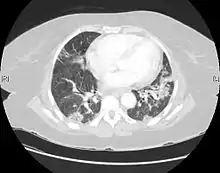

| CT scan of a patient with UIP. There is interstitial thickening, architectural distortion, honeycombing and bronchiectasis. | |

UIP may be diagnosed by a radiologist using computed tomography (CT) scan of the chest, or by a pathologist using tissue obtained by a lung biopsy.

Radiology

Radiologically, the main feature required for a confident diagnosis of UIP is honeycomb change in the periphery and the lower portions (bases) of the lungs.[3]